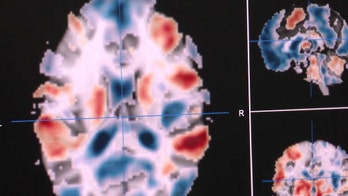

People can consciously control mental activity using brain scans People who can "see" their brain activity can change it, after just one or two neurofeedback sessions, new research shows